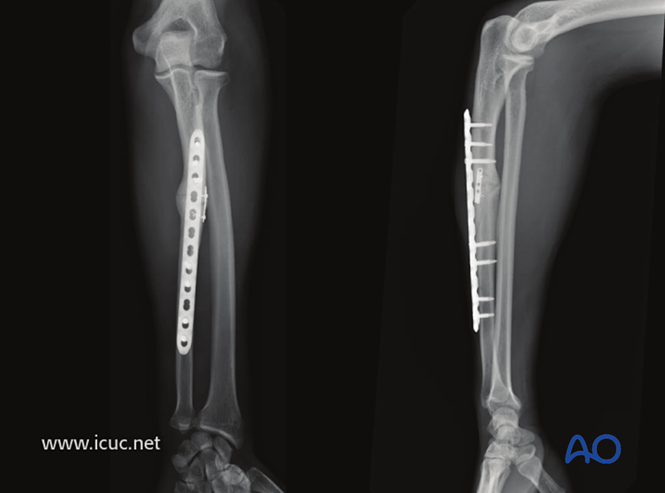

使用很长的锁定加压钢板(LCP)为这一复杂的尺骨中段骨折提供足够的固定。

已完成近端固定,在进行远端固定前,用一把钳子维持复位。

近端和远端均已固定。注意肌肉仍附着在掌侧和背侧表面。仅在50%的螺孔中植入了螺钉。

闭合前的最终固定状态。

采用桥接固定联合复位钢板治疗该复杂孟氏骨折。

遗憾的是,骨折部位存在轻微间隙。如果在固定完成后移除小钢板,愈合可能会更快(见下文)。